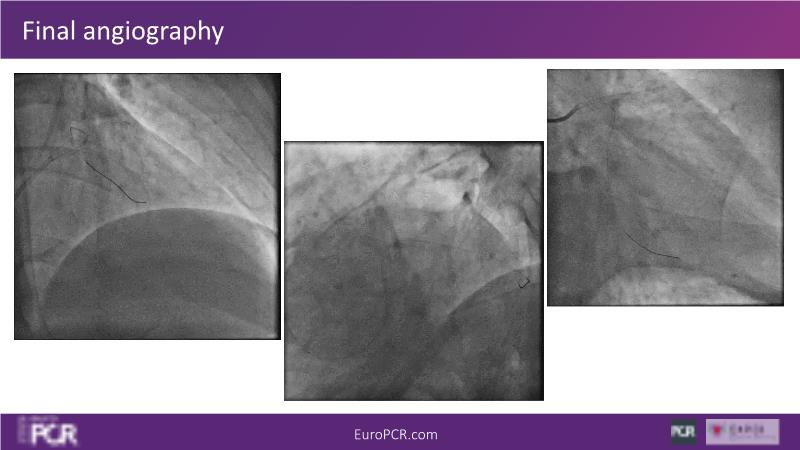

Join this session to delve into the unmet needs concerning drug-eluting stents (DES), including poor long-term clinical outcomes, with up to a 50% MACE rate at 10 years, and a non-plateauing 2-3% annual event rate. Explore how DynamX Bioadaptor technology addresses these challenges by maintaining the established flow lumen and restoring hemodynamic modulation of the artery. Discover the sustained clinical benefits demonstrated in a 2-year RCT, potentially establishing a new treatment standard for CAD patients. Gain insights into patient types benefiting most in clinical practice, such as those at higher risk of restenosis (e.g., LAD disease, long lesions, small vessels, co-morbidities), and younger patients with longer lifespans.

- To understand existing level of broad clinical experience around the world and how clinical decisions are made

- To know the patients and lesions that can be safely and effectively treated with Bioadaptor